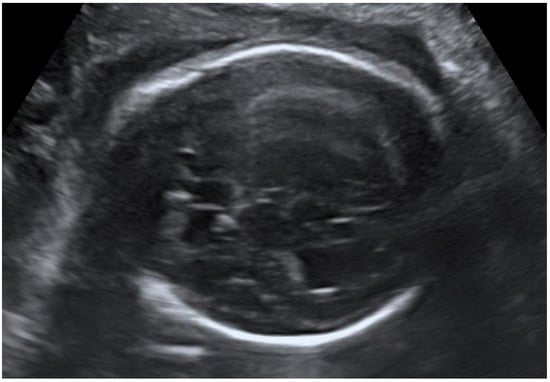

Congenital CMV fetal infection may be associated with a variety of CNS abnormalities. Those may be severe or mild; appear due to the early inflammatory, destructive, and obstructive processes of the brain infection; and directly influence fetal prognosis [60]. Ventriculomegaly (more than 15 mm), microcephaly (a decrease of less than two standard deviations), high echogenicity in the periventricular areas, and hydrocephaly may appear as severe intracranial signs. Increased cisterna magna (more than 8 mm), vermian hypoplasia, periventricular cysts, agenesis of the corpus callosum, lissencephaly, and porencephaly are often associated with congenital CMV infection [4,5,61]. Of these, ventriculomegaly and microcephaly are associated with the worst fetal prognosis. The mild cerebral findings related to fetal involvement include ventriculomegaly enlargement (10 to 15 mm) (Figure 3), intracranial calcifications (Figure 4), cysts of the choroid plexus, subependymal cysts, and intraventricular synechiae [62,63].

Figure 4. Intracranial calcifications; head circumference below the 3rd percentile—microcephaly.